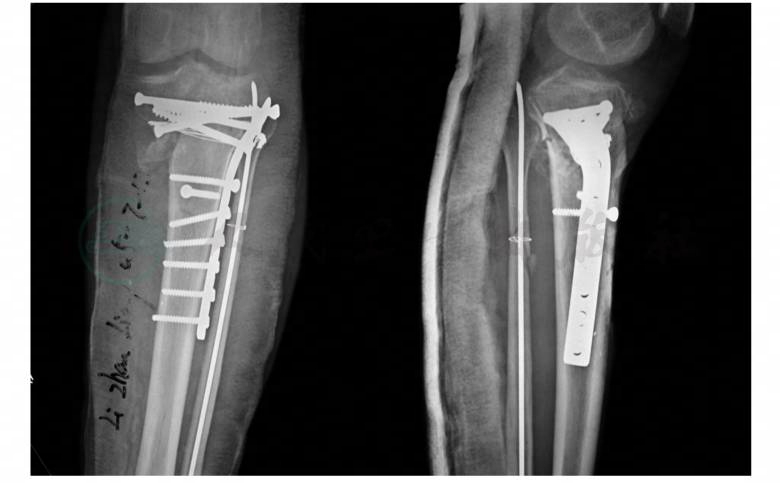

骨科专科情况:左小腿近段前内侧可见一9cm长、最宽为4cm的创面,胫骨前内侧骨质外露。创面外缘可见接骨板,中部有一螺丝钉帽。胫骨内侧面呈暗黄色,远折端向内翘起,表面有少许肉芽组织。骨折近端胫骨骨质呈暗黄色,创面无渗出物(图2)。骨折端无异常活动。膝、踝关节活动正常。足趾远端血运、感觉活动正常。胫骨近段正、侧位X线片示胫骨近段骨折,骨折对位对线好,以接骨板螺丝钉固定。腓骨近段骨折,骨折对位对线好,以一枚克氏针和钢丝环固定(图3)。

图3 入院时X线片